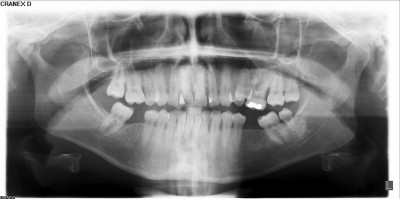

Voltam ma fogászaton , mert ... Mert rendbe akarom szedetni ami nem olyan, amilyennek lennie kéne. Életemben először készült rólam fogröntgen.

Beraktak egy gépbe, rajtam valami ólommmellény, és körbejárt a fejem körül a gép

Kicsit látszik a vámpírfogam is, ami baloldalt a szájpadlásomon nőtt ki.

Jahm meg érdemes lenne fogpótlást csináltatni , mert már dőlnek befele hátul alul a fogaim. Két fogam hiányzik, van viszont egy bölcsességfogam! Hm, vagy kettő? A baloldal elég érdekes.

Fogkőleszedés tuti lesz, meg még ami jön, de ahogy sorolta a dokinő, mindegyiknél azt hallottam szinte, hogy rendben, 1-2-nél mondott valami latin szöveget...

Szülinapomon, reggel 8-kor fogkőlekapás.... -